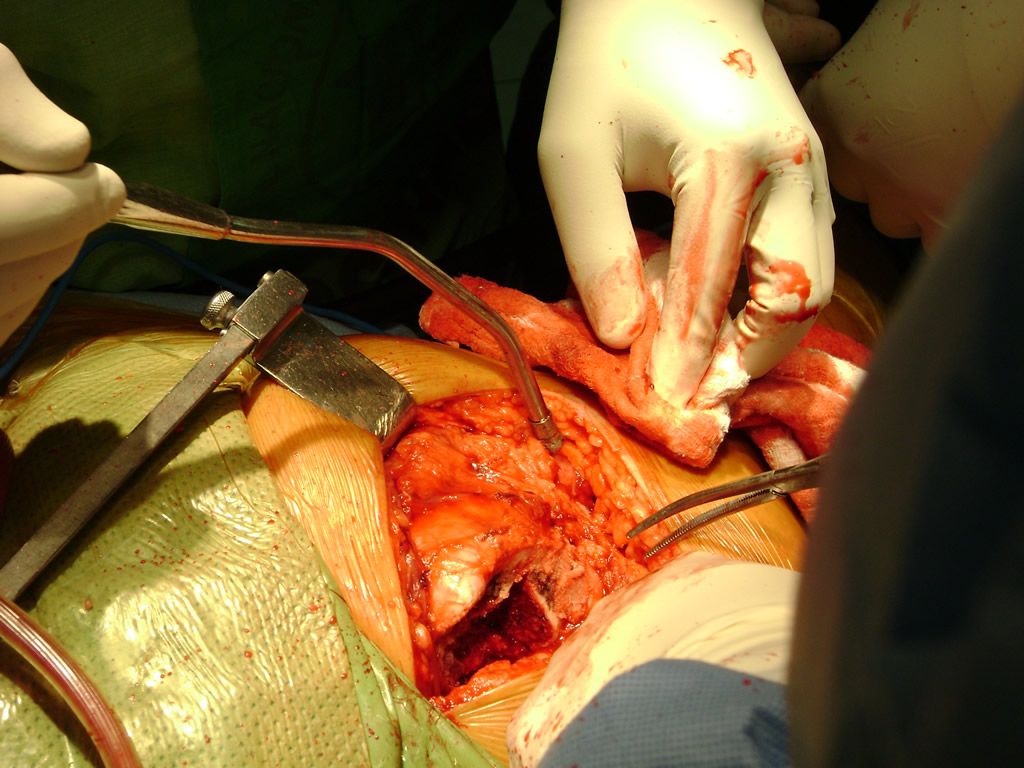

Cirugías

Debido a la fina cobertura de piel que recubre la tibia y el peroné, las fracturas generalmente son abiertas, es decir, el hueso roto rasga la piel, atravesándola. Las fracturas de tibia y peroné generalmente se producen por un fuerte impacto o torsión.